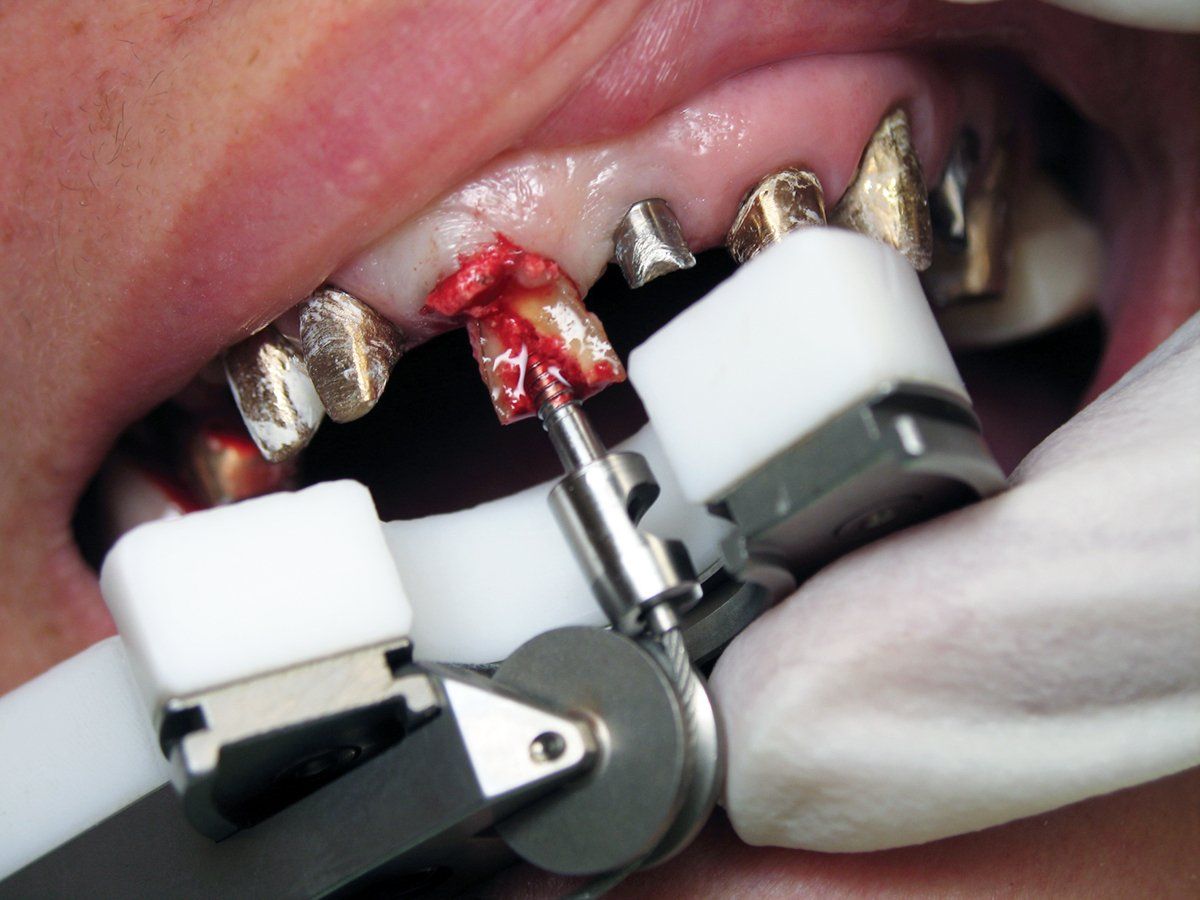

The specific technique involves using a special bur to drill into the pulp chamber and then threading a matching anchor into the tooth (Figure 3). A pulley system is utilized and a protective bite plate rests on the adjacent teeth and is attached to the anchor via a braided cable. By rotating a knob at the end of the instrument, pressure is applied in the vertical axis of the root. As you gently increase the pressure to the cable, it allows the periodontal ligament to stretch. The root is extracted from the socket when sufficient pressure is applied, making a popping noise (Figures 4). When this works, it feels like magic. Left behind is an intact socket with the soft tissue and bone preserved and ready for immediate placement of a dental implant (Figure 5).